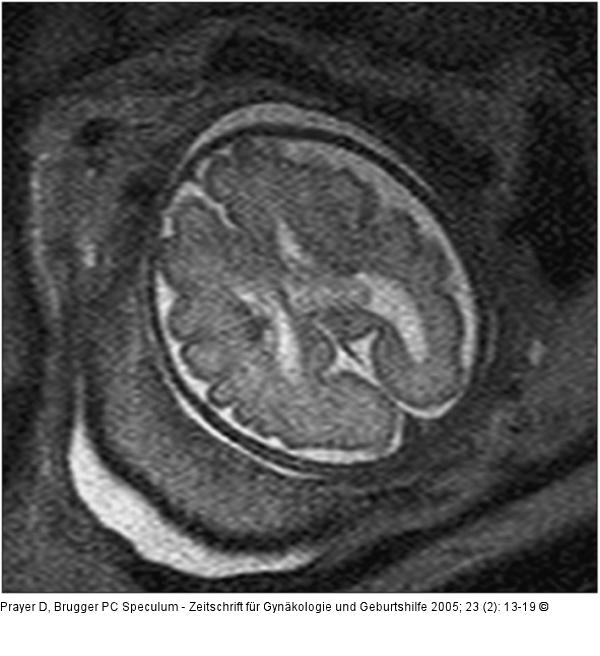

Abbildung 5: Pränatale Magnetresonanztomographie 30. SSW, axiale Schichtführung. Auf der linken Bildseite zeigen sich, am Rand des Seitenventrikels gelegen, zwei dunkle Knötchen, die subependymalen Riesenzellastrozytomen entsprechen, und für das Vorliegen einer tuberösen Sklerose pathognomonisch sind. |

30. SSW, axiale Schichtführung. Auf der linken Bildseite zeigen sich, am Rand des Seitenventrikels gelegen, zwei dunkle Knötchen, die subependymalen Riesenzellastrozytomen entsprechen, und für das Vorliegen einer tuberösen Sklerose pathognomonisch sind. |